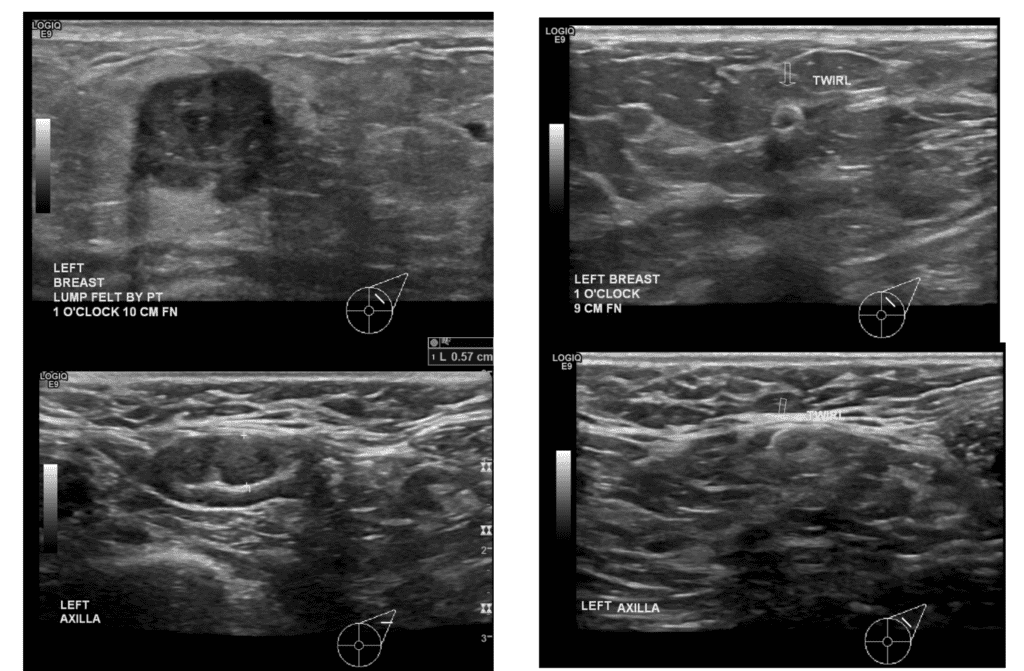

Ultrasound images showing abnormal mass (upper left) and abnormal lymph node (lower left) at patient presentation. After chemotherapy, there was no mass visible in the breast (upper right) and the lymph node had normalized in appearance (lower right).

Chemotherapy prior to breast surgery allows the patient to undergo life-saving treatment first as well as be a candidate for breast conserving surgery after.